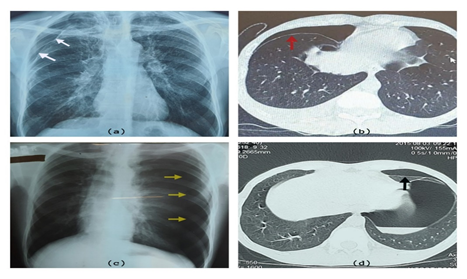

A 42-year-old non-smoking male with a history of multiple spontaneous pneumothoraces (which had been treated with pleurectomy) was referred to our tertiary center with sudden onset difficulty in breathing and right-sided pleuritic chest pain. He was found to have a large right-sided pneumothorax managed initially with intercostal chest drain (ICD). Following the drain insertion, patient’s breathing improved and the lung expanded. Despite that, he continued to have a small residual pneumothorax (<2cm) (Figure 1a & b).

After three years the first diagnosis of WD, the patient developed left-sided recurrent PSPs (Figure 1c & d), where he ended up in video assisted thoracoscopic (VATS) guided left-side pleurectomy in 2015. Since then, he has been stable until the current presentation.

Figure 1 a & b illustrates the current presentation with right side residual pneumothorax in CXR (white arrows) and HRCT of the chest (red arrows). c & d -illustrate past-left sided pneumothorax in CXR (yellow arrows) and HRCT (black arrow).